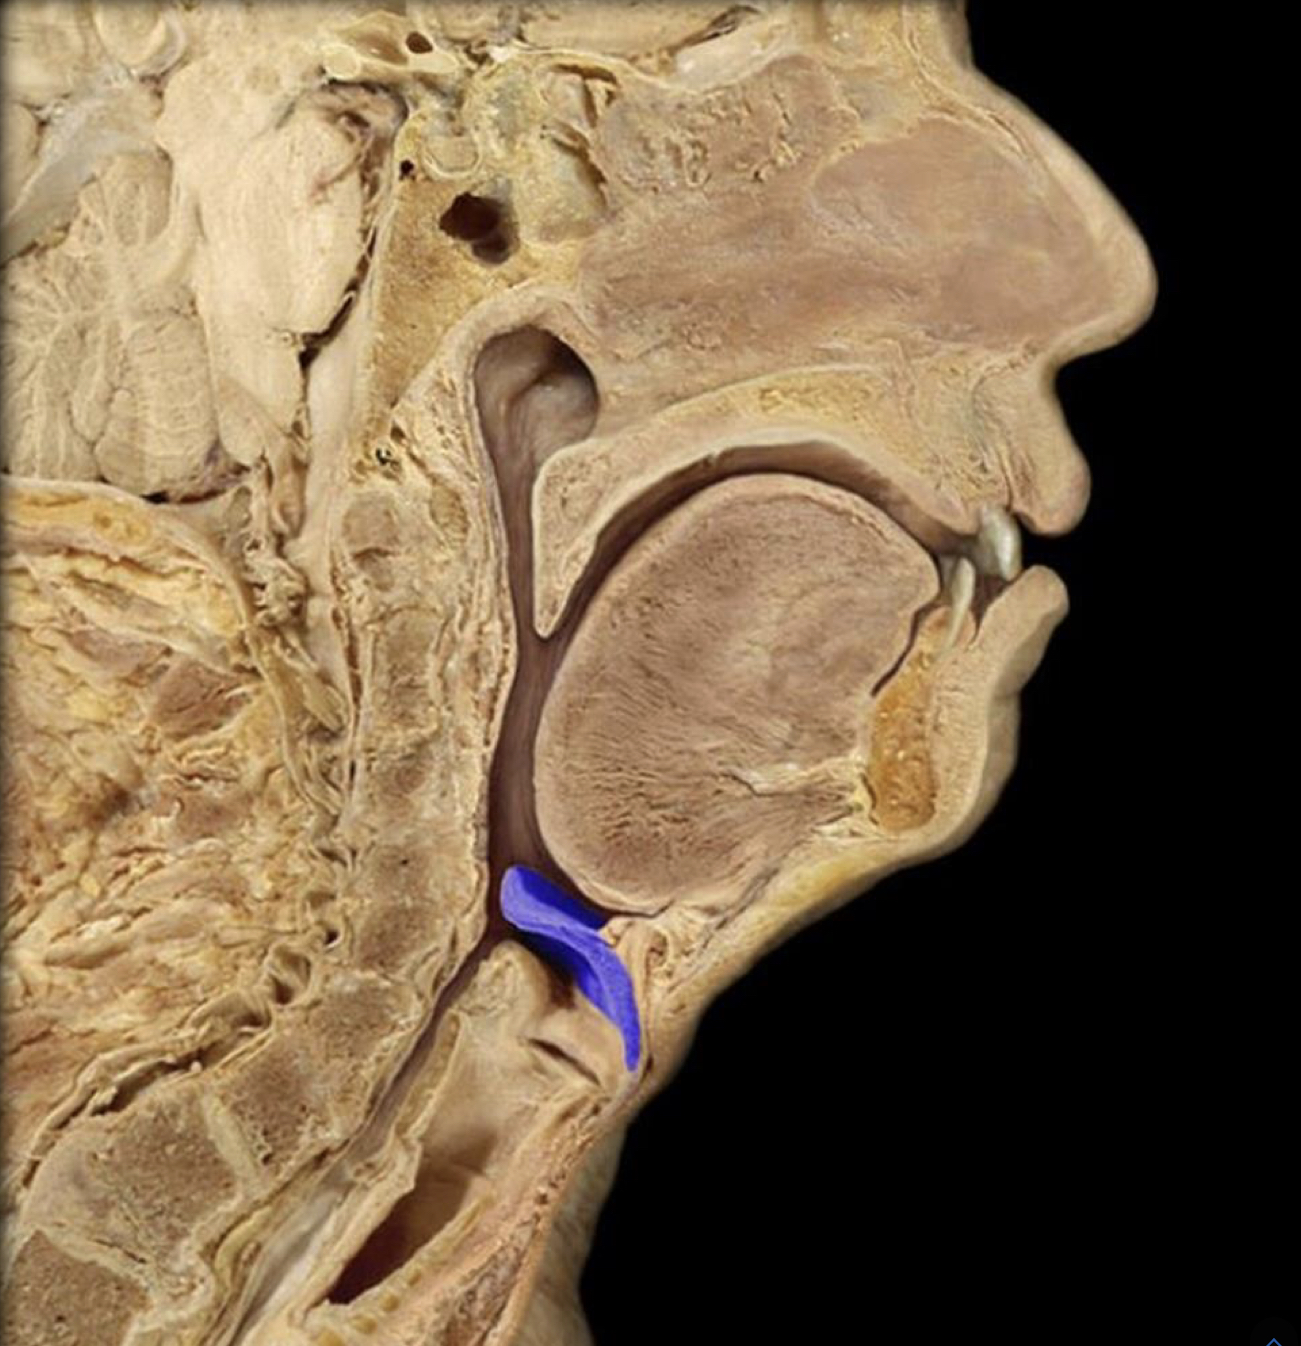

Epiglottis

Epiglottis (lateral view)